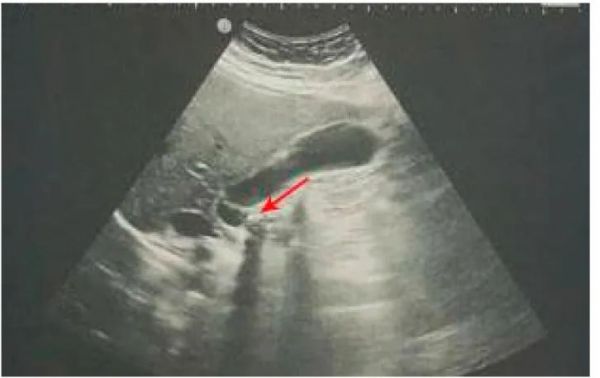

胆石症诊断的金标准(图 3)是美国的一项检查[53],对孕妇尤其重要,因为该手术不使用电离辐射[49]。此外,研究表明,POCUS对检测胆石症具有很高的敏感性(89.8%)和特异性(88%)[54],但也可以检测胆汁污泥,这是胆结石形成的初始阶段[49]。

图 3胆囊颈部的阻滞内结石(红色箭头)。

直径小于5 mm的胆结石表现为无后声阴影的高回声焦点[55],而直径大于5 mm的胆结石表现为高回声焦点,伴有后声影和回声边缘[3]。美国体格检查显示的急性胆囊炎的体征为胆囊肿大、壁增厚(厚度大于4mm)和分层、胆汁淤泥和腔内胆结石、胆囊积液和墨菲氏阳性征(右肋弓下对探针压力的敏感性疼痛)[16,56,57]。在POCUS期间检测与墨菲氏阳性征相关的胆结石对急性胆囊炎的阳性预测值为92%[51]。如果美国体格检查显示生理性胆囊壁和生理性胆总管,可排除急性胆囊炎[49]。